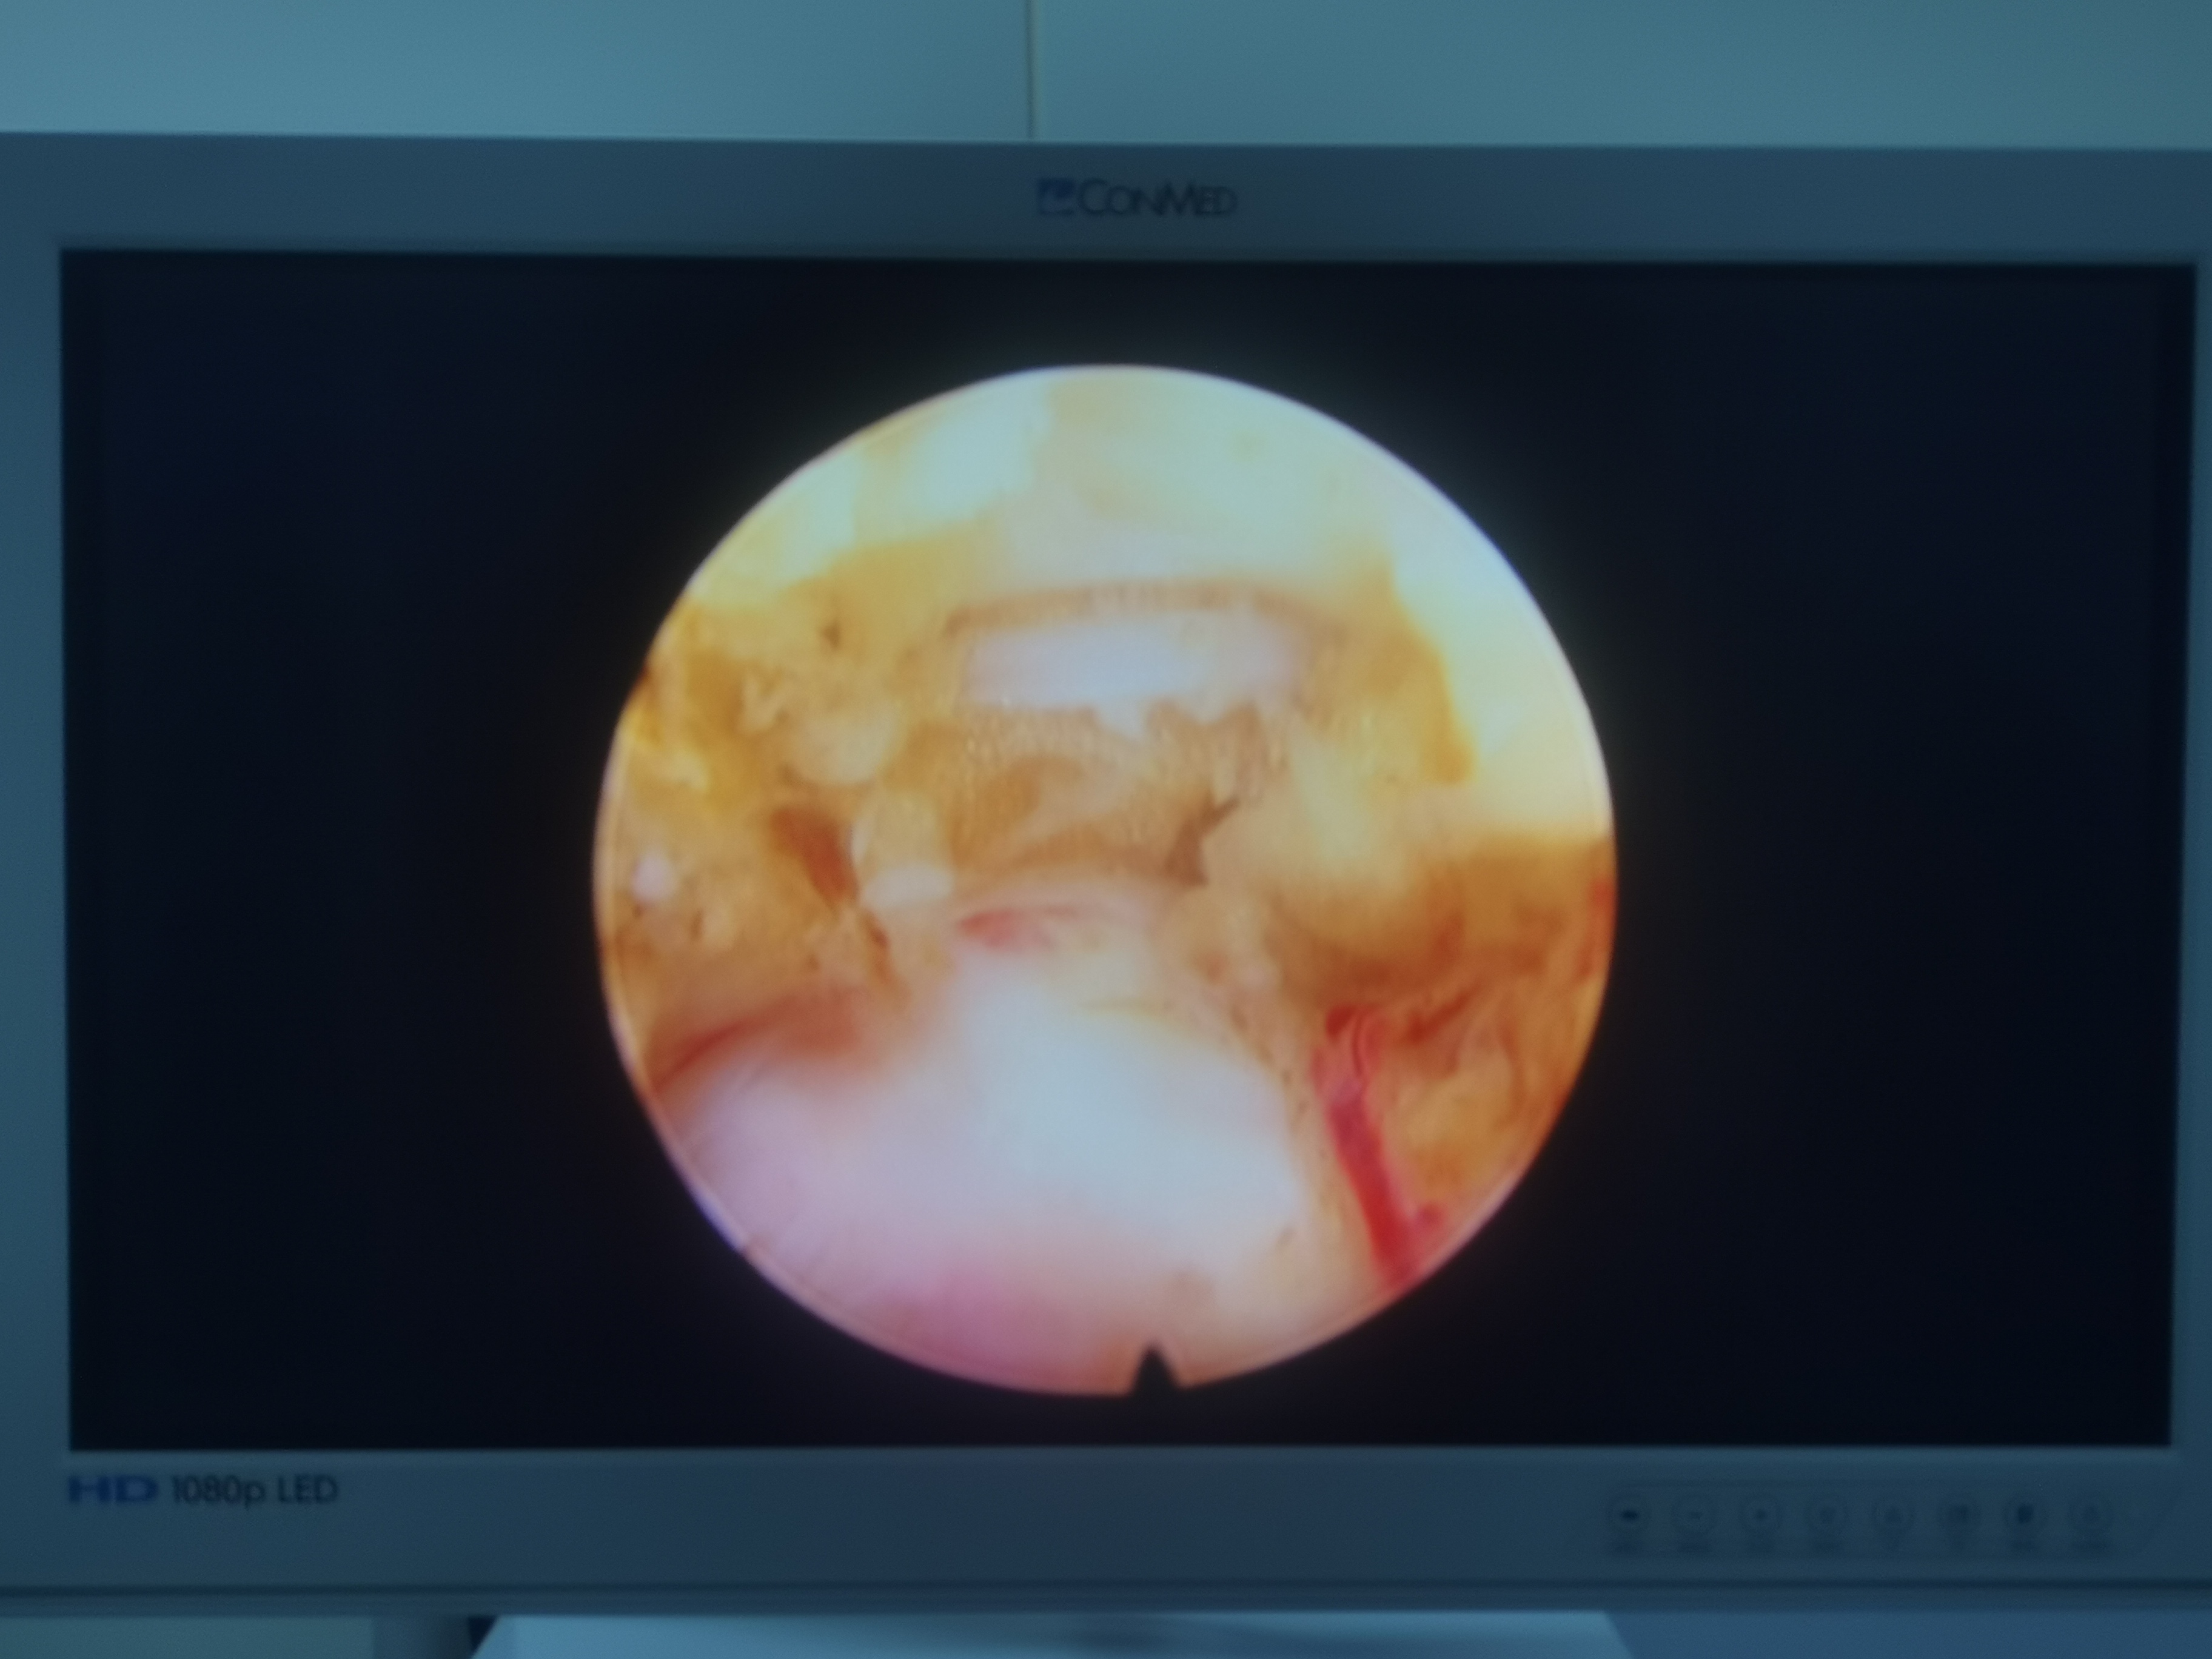

- 椎间孔镜微创术:适合年轻患者,开个7毫米的小口,用“电子吸管”精准吸走突出物,术后3天就能下床。缺点是5年内有约8%的复发率,就像补牙后仍要注意护牙。